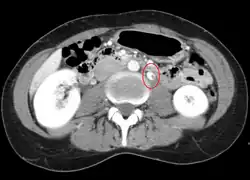

Observing the patient's symptoms, medical history and imaging remain the fundamental source for diagnosing RVT. Imaging is used to detect the presence of a blood clot. In an abnormal kidney with RVT, a blood clot is present in the renal vein. In cases where the renal vein is suddenly and/or fully blocked, the kidneys will enlarge, reaching its maximum size within a week. An ultrasound imaging can be used to observe and track the size of the kidneys in RVT patients. Ultrasound is not efficient for use in detecting blood flow in the renal veins and artery. Instead a color doppler ultrasound may be used to detect renal blood flow. It is most commonly used to detect RVT in patients who have undergone renal transplantation. CT angiography is currently the top choice in diagnosing RVT. It is non-invasive, relatively cheap and fast with high accuracy. CT scanning can be used to detect renal enlargement, renal tumors, blood flow and other renal pathologies. An alternative is magnetic resonance angiography or MRA. It is non-invasive, fast and avoids radiation (unlike a CT scan) but it is relatively expensive. MRA produces detailed images of the renal blood flow, vesicle walls, the kidneys and any surrounding tissue. An inferior venocavography with selective venography can be used to rule out the diagnoses of RVT.[6]